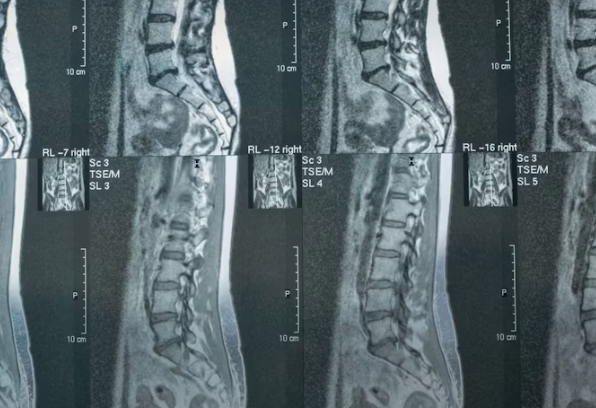

MRIやレントゲンは、骨や椎間板など、構造的な変化を見るための検査です。

ただ、画像に映らないものがある。

筋肉や筋膜(ファシア)といった軟部組織の状態異常は、通常の画像診断ではほとんど見えません。硬くなっているか、滑走が悪くなっているか、過敏になっているか——そういった「組織の質の変化」は、画像では判断できない。

だから「画像に異常がない=痛みの原因がない」とはならない。実際に痛みを出している組織が、画像に映らない場所にある、というケースは珍しくないのです。